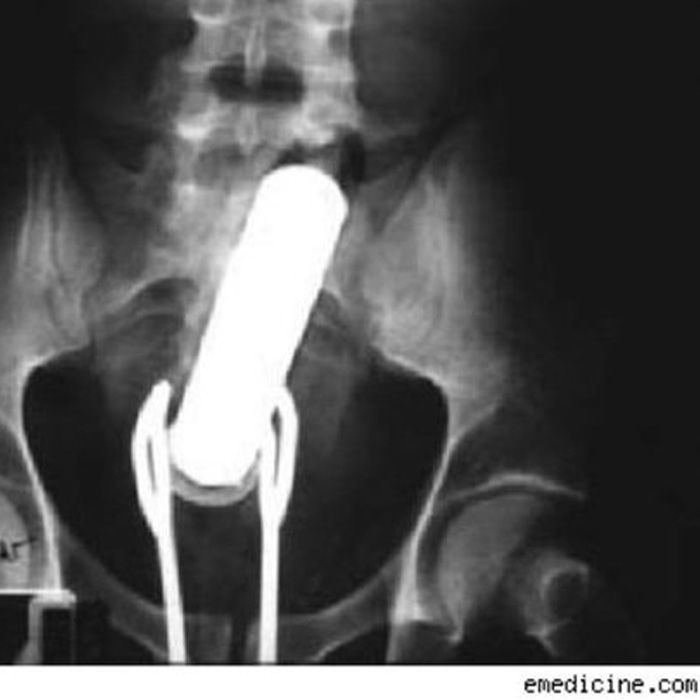

The vibrator that got stuck up there is finally something “normal”. The salad tongs to get it back out again … not so much. I’m sure there is a tossing salad joke in there somewhere.